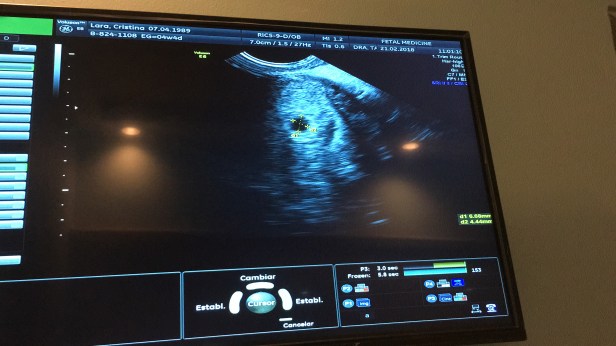

Hace unas semanas atrás me enteré que estoy embarazada, y he estado llena de muchos miedos y dudas. No solo por la posibilidad de tener otra perdida (en este post te cuento sobre nuestra perdida) sino también por todo lo que conlleva otro bebe en la familia.

Por otro lado ha sido un embarazo algo difícil pues he estado con muchos malestares, desde las nauseas a cada rato, aunque gracias a Dios ya se fueron, dolores de espalda y cadera, migrañas, falta de apetito, ganas de orinar cada 5 minutos, falta de aire, mucho sueño. La pansa también se ha crecido un montón y aveces me pregunto si el doc se equivocó y vienen dos en vez de 1 porque no entiendo como estoy tan grande con apenas 16 semanas. Mi ropa pre-embarazo no me queda por lo cual empecé a usar mis pantalones de embarazada hace como 2/3 semanas atrás.